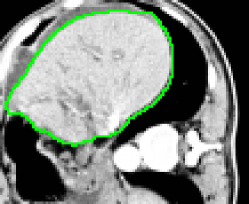

4.1 Metrication artifacts and minimal surfaces

We begin by comparing the CCMF segmentation result with the classical max-flow algorithm (graph cuts). Figure 3 shows the segmentation of a brain, in which the contours obtained by graph cuts are noticeably blocky in the areas of weak gradient, while the contours obtained by both AT-CMF and CCMF are smooth.